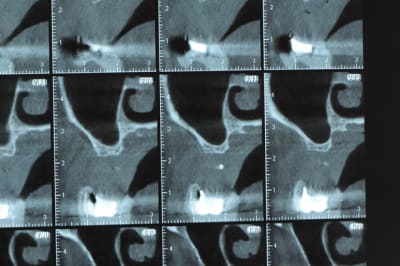

Ce n'est pas vraiment un consensus mais plutot du bon sens. Si tu as une crête en profil de lame de couteau cela signifie que tu as une fusion des corticales vestibulaire et palatine et donc absence de spongieux, ce qui comme tu le sais n'est pas indiqué en implanto (cj os de marbre par exemple)

Il me semble que Palti ou encore Szmukler-Moncler recommandent un minimum de 2-3mm. Si c'est plus fin, greffe d'apposition et GBR.

Dans ton cas il te faudrait abaisser la crête de 3 bons mm pour arriver à cette épaisseur.

Ce n'est pas vraiment un consensus mais plutôt du bon sens. Si tu as une crête en profil de lame de couteau cela signifie que tu as une fusion des corticales vestibulaire et palatine et donc absence de spongieux, ce qui comme tu le sais n'est pas indiqué en implanto (cj os de marbre par exemple)

Il me semble que Palti ou encore Szmukler-Moncler recommandent un minimum de 2-3mm. Si c'est plus fin, greffe d'apposition et GBR.

Dans ton cas il te faudrait abaisser la crête de 3 bons mm pour arriver à cette épaisseur.